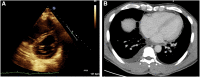

Figures